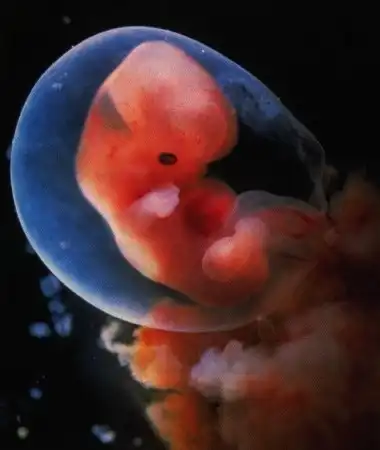

У мамы в животике)